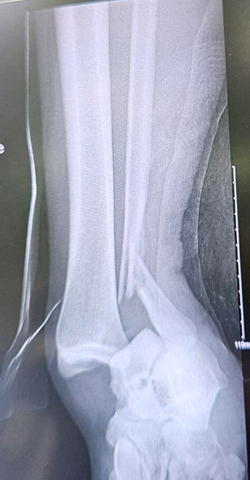

ORIF Ankle Fracture Dislocation

Ankle fracture surgery is a procedure to treat a broken or fractured ankle. An ankle fracture is a painful condition where there is a break in one or more bones forming the ankle joint. Ankle fracture surgery typically involves realigning and stabilizing the fractured bones using metal implants like plates, screws, or rods to allow proper healing and restore function.

The ankle is a hinge joint formed by three bones: the tibia, fibula, and talus. The tibia and fibula are the two bones of the lower leg, and they form a socket that holds the talus bone of the foot. The bony bumps felt on either side of the ankle are the medial malleolus (tibia) and lateral malleolus (fibula). Ligaments connect these bones and provide joint stability, while tendons attach muscles to bones and control movement. The ankle allows up-and-down motion of the foot and plays a key role in walking, running, and balance.

During ankle fracture surgery, the surgeon realigns and stabilizes broken bones in the ankle using metal hardware – a type of surgery referred to as open reduction and internal fixation (ORIF). In general, the procedure involves the following steps: